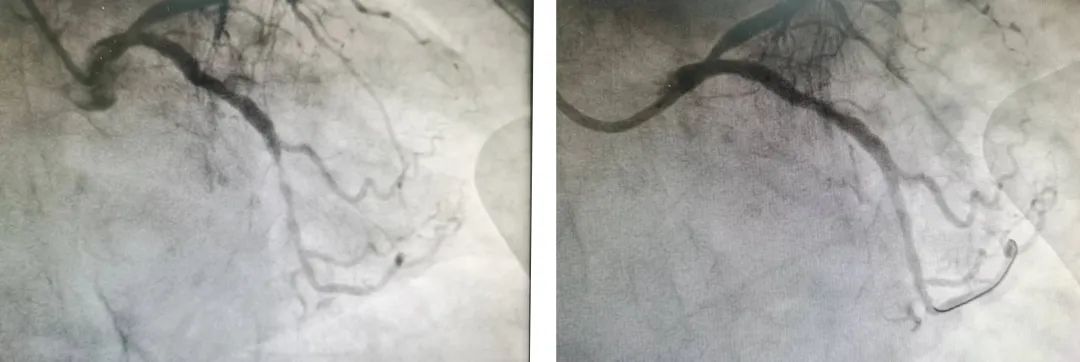

在予以利尿、扩血管、抗血小板聚集、降血脂稳定斑块等药物治疗后,黄阿婆胸闷气促的症状稍有改善,咳嗽明显好转。在病情稳定后,心内科团队再行冠状动脉造影检查,检查结果提示为冠心病 及三支病变。在前降支支架植入术后,可见支架内膜增生,回旋之远段狭窄80%,右冠不规则狭窄30-70%。

在冠脉造影前,黄阿婆反复交代“只做造影、不做支架”,在冠脉造影后,我院团队明确了回旋支远段严重狭窄,为“罪犯血管”。

唐疾飞主任团队再次仔细评估后,决定采取“经皮冠状动脉药物球囊扩张成形术”,无需植入支架,又能达到植入支架的效果。在取得患者本人同意及电话告其家属后,成功对回旋支远段行“药物球囊”扩张成形术。术后,黄阿婆胸闷气促的症状逐渐缓解,并自诉“咳嗽”顽疾好了80%!

▲术前(左)术后(右)影像资料